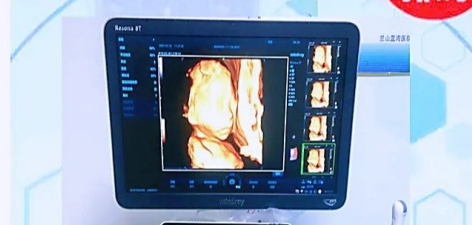

迈瑞8T高端五维立体彩超仪

迈瑞8T五维彩超仪最大的亮点在于ZST+域光平台及域成像技术,让画质更细腻,成像效果更清晰,能够超越过去所有四维彩超系列。过去的四维彩超只能看到宝宝大致的轮廓,但使用迈瑞8T高端五维立体彩超仪就不同了,它提供了前所未有的成像质量及许多先进的超声成像功能,可以完美实现孕妈和宝宝的“隔空对话”,高清动态画质堪比“IMAX电影”,360°超真立体展示宝宝的实时活动图像。